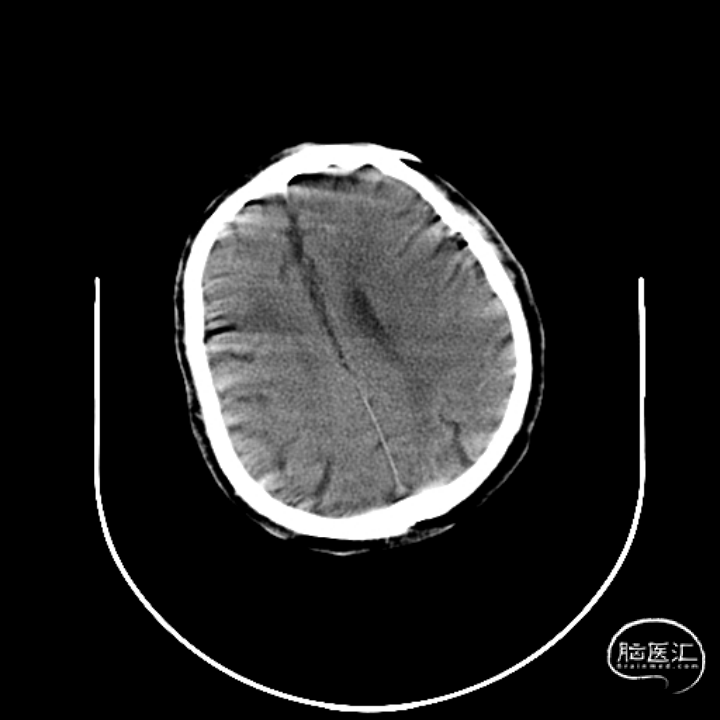

术前CT

现病史:患者于1天前突发吐字不清、左侧肢体活动不灵,左上肢尚可抬举、握拳无力,左下肢无法站立及行走,伴腹部疼痛,无明显头晕头痛,无恶心呕吐,无复视耳鸣,无吞困难,急来我院急诊就诊,急诊行头CT提示未见出血,患者病来神清,无发热,无咳咳,无胸闷及胸痛,无腹痛腹泻,无黑便。平素饮食可及睡眠尚可,二便正常。

既往史:脑出血病史约8-9年,遗留吐字欠清、左侧肢体活动不灵,左上肢尚可抬举及持物,左下肢行走无拖电。冠心病、陈旧性心肌梗死、冠状动脉支架植入后状态病史约12年,规律口服1年阿司匹林肠溶片及“立普妥”后自行停药,高血压病病史约8-10年,已自行停药2年,否认糖尿病病史,否认肝绕结核等传染病史,否认手术外伤史输血史,头孢过敏史,否认食物过敏史。

入院查体:嗜睡,言语欠清,双侧瞳孔等大正圆,直径3.0mm。直接间接对光反射灵敏,双眼各向活动正常,右侧鼻唇沟浅,伸舌右偏,左侧肢体肌力5级,右侧上肢0级,下肢肌力3级,右侧巴氏征阳性。急诊NIHSS评分:9分。